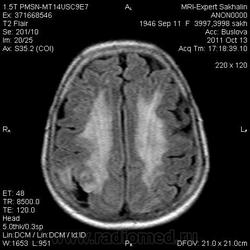

Ишемический инфаркт

Вот, Сергей Николаевич, я тоже указала, что НМК по ишемическому справа в СМА

ОНМК по ишемическому типу в бассейне правой СМА. Судя по очагам накопления в коре, подострое.

Последствия ОНМК с геморрагическим пропитыванием справа. Кистозно-атрофические изменения в левой гемисфере мозжечка (последствия ОНМК ). Множественные очаги сливного характера вещества головного мозга ( поля лейкоариоза)

Да хотела еще добавить возможно у пациента еще были лакунарные инсульты. В области базальных ядер( слева ) определяются кисты, окруженные глиозом. И на предпоследнем изображение в правой гемисфере мозжечка по- моему и также есть нмк.

Гглиоз, сосудистые очаги, лейкоареоз - это все при ДЭП, этим и обусловлена деменция.

Да наверное все это можно одним словом сказать дэп (хнмк). Но для невролога лучше наверное стоит дать полною описательную картину. Они как правило редко снимки смотрят, что чем более подробное описание, тем более понятна им будет картина.

Танюша, все указала-и лакунаные постишемические кисты, и кистозно-глиозные левой гемисферы мозжечка.Правая , вроде бы, не задействована в процессе.